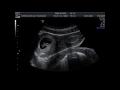

Качество яйцеклеток может оказать влияние на возможность зачатия и успех беременности у женщин после 40 лет. В этом возрасте яйцеклетки могут иметь больше шансов на изменения в ДНК и хромосомах, которые могут привести к различным генетическим аномалиям.

Помните, что возможность зачатия и успешной беременности после 40 лет может зависеть от множества факторов, включая генетику и общее здоровье. Важно консультироваться с медицинским специалистом, чтобы получить персонализированную информацию и рекомендации, учитывающие ваши уникальные обстоятельства.